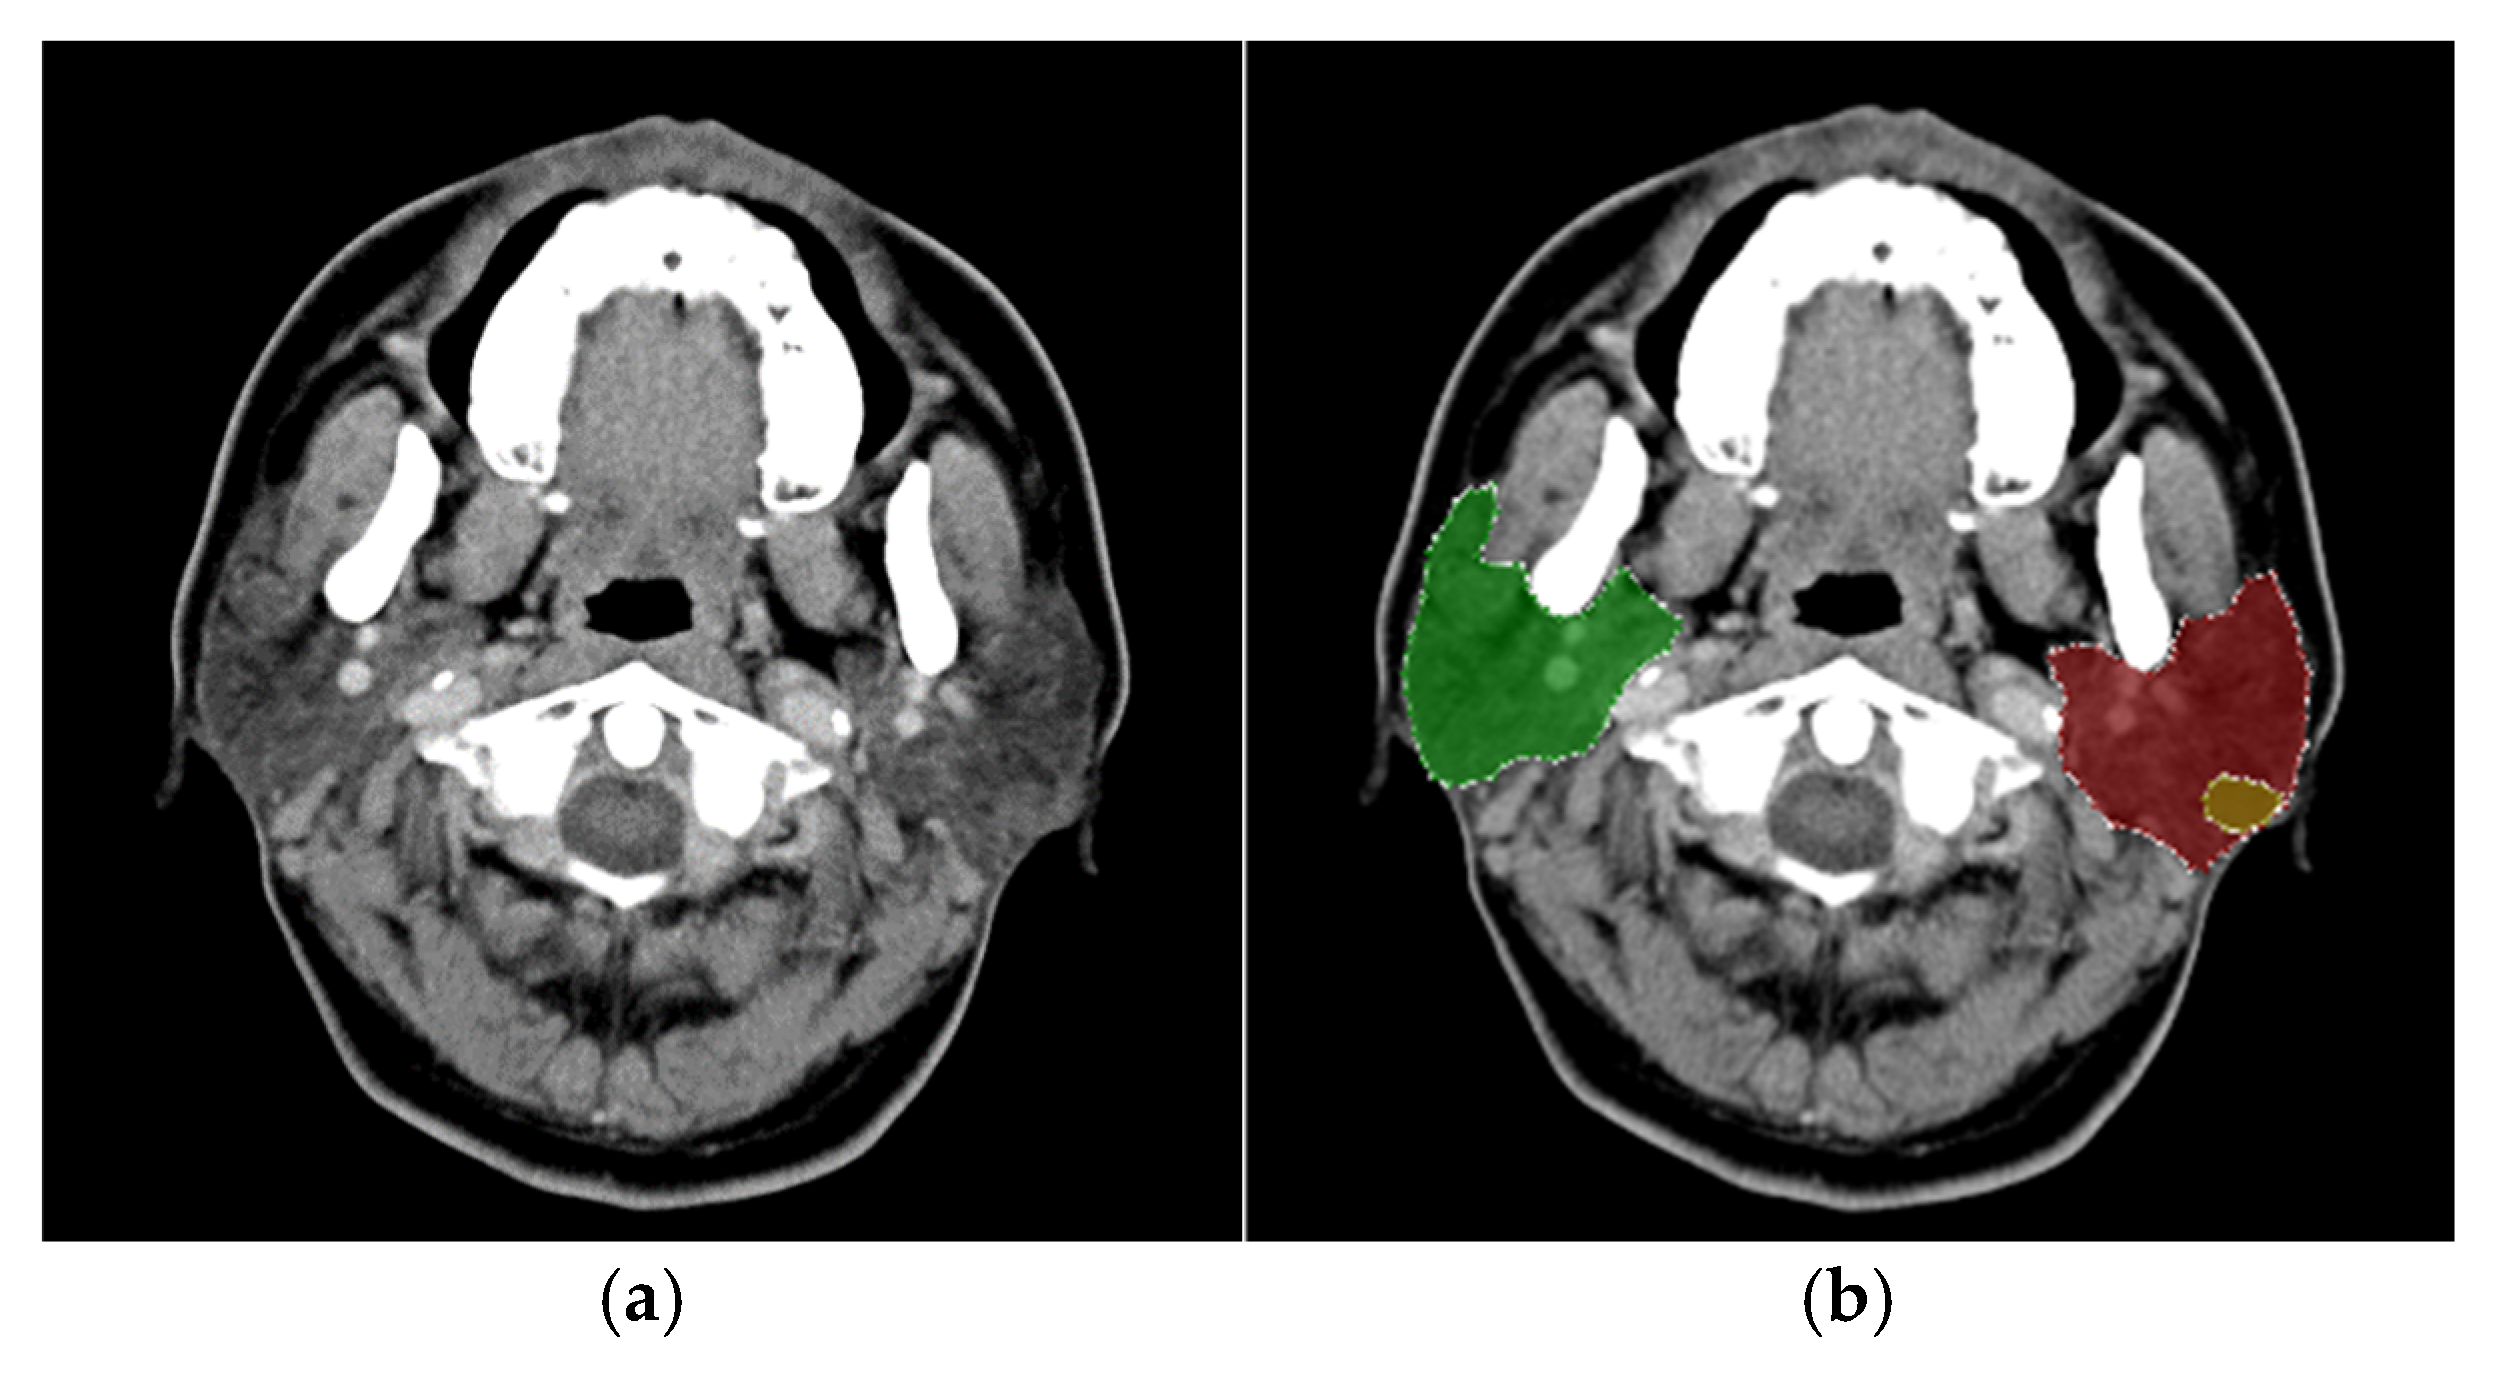

In this study, head and neck CT images were sourced from the ENT CLINIC of National Cheng Kung University Hospital. All scans were performed using the SOMATOM Definition AS (Siemens, Germany) with the following parameters: tube current set to CARE Dose 4D quality reference at 180 mAs, tube voltage at 120 kVp, slice thickness and interval of 5 mm, and a display field of view of 22 cm. The scanning range extended from the skull’s base to the thoracic cavity’s entrance. Enhanced images were acquired following the intravenous injection of 60–100 mL of contrast agent (350 mg/mL; Xenetix®, Guerbet, Villepinte, Paris, France) at a rate of 2.0 mL/s, followed by 20 mL of normal saline. The captured images had a 512 × 512 resolution pixels with a pixel width of 0.41 mm. The experimental dataset comprised 4,183 CT images, of which 3,436 were labeled, while 747 remained unlabeled due to the absence of identifiable parotid glands. The dataset included 232 patients, consisting of 64 diagnosed with malignant tumors and 168 with benign tumors. The gender distribution was predominantly male, with a male-to-female ratio of 6:4; the average patient age was 66 years. An original CT image is presented in Figure 2a.

For this study, the LabelMe software [11] was used to assist physicians in annotating the locations of parotid glands and tumors, resulting in bounding boxes for each identified structure. The annotations were categorized into eight distinct classes: left parotid gland, right parotid gland, left malignant tumor, right malignant tumor, left mixed tumor (pleomorphic adenoma), right mixed tumor (pleomorphic adenoma), left Warthin tumor, and right Warthin tumor, as illustrated in Figure 2b. The diagnostic process for classifying tumor types considered factors such as lesion distribution, shape, density, and margins. Clinical observations have noted that pleomorphic adenomas (mixed tumors) carry a potential risk for malignant transformation, whereas Warthin tumors are associated with an extremely low likelihood of malignancy.

Figure 2. (a). Original image. (b). Labeled CT image with annotated regions.